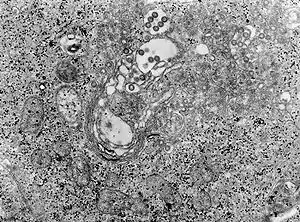

![]() TEM micrografe a țesutului infectat cu virusul febra VAII Marelui Rift | |